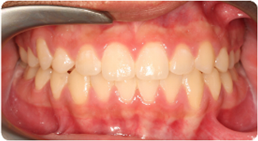

Each case shows the front view and an arch or side view, before and after BioLign Method-guided treatment.

All cases treated within 6–12 months.

Misaligned lower arch corrected with coordinated expansion